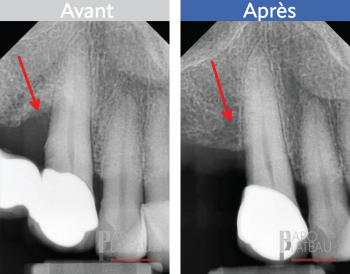

La greffe osseuse

Cette procédure consiste à corriger une déficience osseuse localisée. Cette dernière peut avoir été causée par une parodontite ou un incident local. Nous ajouterons de l’os et une membrane généralement faite de collagène pour combler ce manque.

Avant

Après